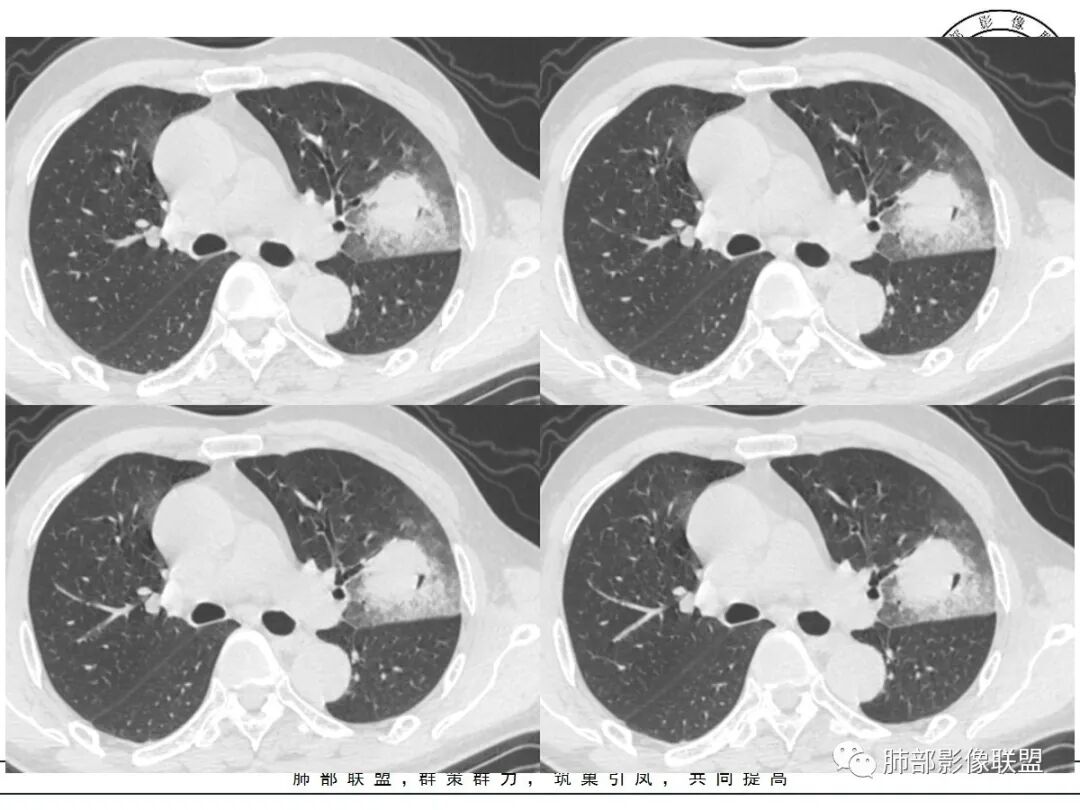

左肺上叶类圆形软组织影,边界较清楚,其内密度均匀,外侧缘可见空气新月征,并可见点状钙化,增强扫描可见均匀强化,病灶周围可见磨玻璃渗出性密度影,斜裂侧光滑平整。考虑炎性病灶,以肉芽肿性炎症为主(如真菌性肉芽肿),鉴别结核(无卫星灶,无多态性),肺癌(无毛刺,分叶等恶性征象,)细菌性炎症(密度一般不这么致密,很少钙化及空气新月征)。

老年男性,血糖升高六年,反复咳痰咳嗽3周,左肺上叶近斜裂类圆形肿块影,边缘伴磨玻璃影,边界不清。内部可见支气管走行、钙化、小空洞,叶间裂局部膨隆,增强扫描轻度强化,内部可见小的低密度区,边界尚清。考虑为炎性病变可能性大。

左肺叶裂旁实变影,宽基底与叶裂胸膜相连,边缘平直,部分略膨隆,病灶近段及上段支气管深入病灶内,部分壁略增厚,远端支气管截断,似有小空泡,壁规则,内部可见高密度钙化,周围可见模糊的GGO,血象正常,考虑结核(NTM),鉴别隐球菌,奴卡,放线菌。

胸部CT:左肺上叶类圆形肿块影,边界较清楚,密度较均匀,内可见小片坏死、偏心空洞、空气新月征、点状钙化,周围晕、絮状渗出、边缘模糊,支气管扩张、充气征、支气管进入病灶堵塞,叶裂牵拉明显,增强扫描中度均匀强化,纵隔可见淋巴结。考虑:炎性病灶,肉芽肿性炎症,曲霉?毛霉?鉴别:TB,淋巴瘤。

左上肺类圆形肿块影,边界较清楚,支气管通畅略扩张,周围磨玻璃影,其内密度均匀,外侧见空气新月征,且见点状钙化。叶间裂光滑稍膨隆。老年男性,糖尿病,高血压,痰培养克雷伯菌。综合考虑炎性病灶,克雷伯合并真菌感染,曲霉。结核合并真菌。鉴别肺癌合并感染。

左肺上叶类圆形软组织影,边界稍模糊,其内密度均匀,外侧缘可见空气新月征,并可见点状钙化,增强扫描渐进性强化,病灶周围可见磨玻璃影,斜裂侧光滑平整,气管未见明显闭塞,淋巴结未见肿大,糖尿病患者,首先考虑感染性变,结核并曲霉?

1、团片状,实行密度区外观整体圆顿,位于上叶尖后段与下舌段区间。局部膨隆,但未见分叶,肿瘤多见。

5、周围磨玻璃,3个月后逐渐转为密实,应符合当初附壁生长为主,且逐渐向实体成分转换。

6、病变长轴平行且受限于胸膜,外围大内带小,符合外朝内发展病变。“腔内结节状明显强化”加之支气管改变有力支持新生物诊断。如此大范围边界不清的磨玻璃影让人浮想联翩。如此大范围病灶,肺门纵隔未见肿大淋巴结也让人意外。

1、外周分布(起源外围由外朝内发展蔓延);

2、实变和磨玻璃阴影特点;

3、病理性支气管充气征;

4、实变内有密度较低、强化较低区;

5、“假空洞”/“蜂窝征”;

6、周围小结节,树芽征少;

8、间质增厚改变;

11、胸膜改变:糊墙征;

12、前后对比进展:病灶增大、GGO区实变。